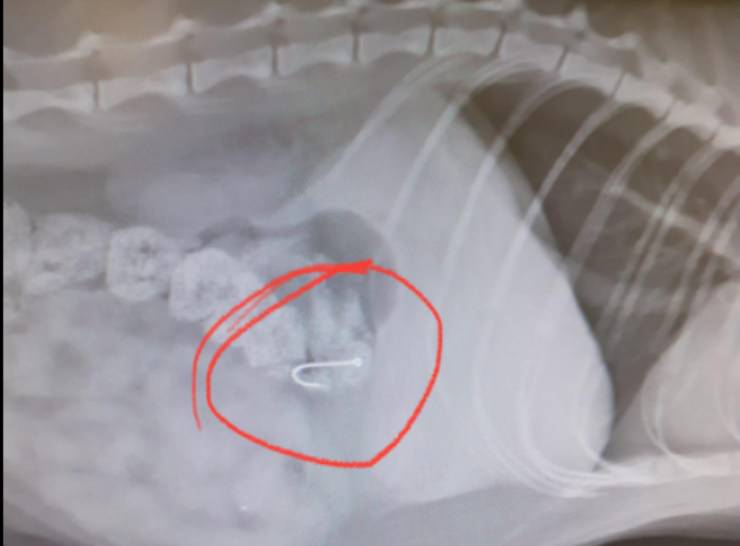

Diverse persone infatti hanno notato il micio in difficoltà ed hanno segnalato il caso. White aveva l’amo in bocca e stava cercando di liberarsene da solo. Purtroppo però, dopo l’ennesimo tentativo, il micino ha ingerito l’amo ed ha rischiato una perforazione dello stomaco.

L’intervento della volontaria e la corsa dal veterinario lo hanno salvato dal peggio. La donna di nome Susanna era impegnata nei festeggiamenti di un compleanno ma, non appena ha ricevuto la segnalazione, si è precipitata ad aiutare il pelosetto bianco. La volontaria è un angelo custode a cui White sarà di certo grato per sempre.